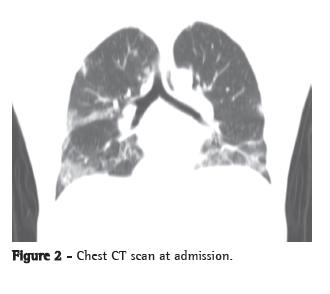

A chest X-ray showed worsening of the bilateral alveolar infiltrate, and a chest CT scan showed multifocal ground-glass infiltrate (Figures 1 and 2).

The most common radiological manifestations of influenza pneumonia consist of reticulonodular opacities, with or without superimposed areas of consolidation. Less commonly, patients with influenza pneumonia can present with focal areas of consolidation, typically in the lower lobes, without apparent reticular or reticulonodular opacities. The radiological abnormalities typically resolve in approximately three weeks. Consolidations can occur due to secondary bacterial pneumonia.(7,8)

On chest CT scans, various patterns are possible. However, the ones most commonly reported are those showing lobular areas, typically bilateral, of ground-glass attenuation. Other possible patterns are the presence of focal areas of consolidation, centrilobular nodules and the tree-in-bud pattern.(9)